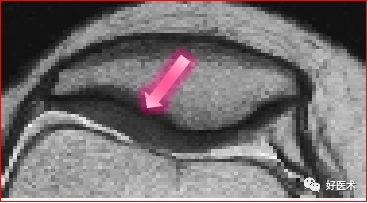

chondromalacia 软骨软化分级

1级 浅表病变,软骨变软

2级 浅表病变累及软骨深度约50%

3级 软骨病变累及软骨深度>50%,但未达软骨下骨

4级 软骨破坏并累及软骨下骨